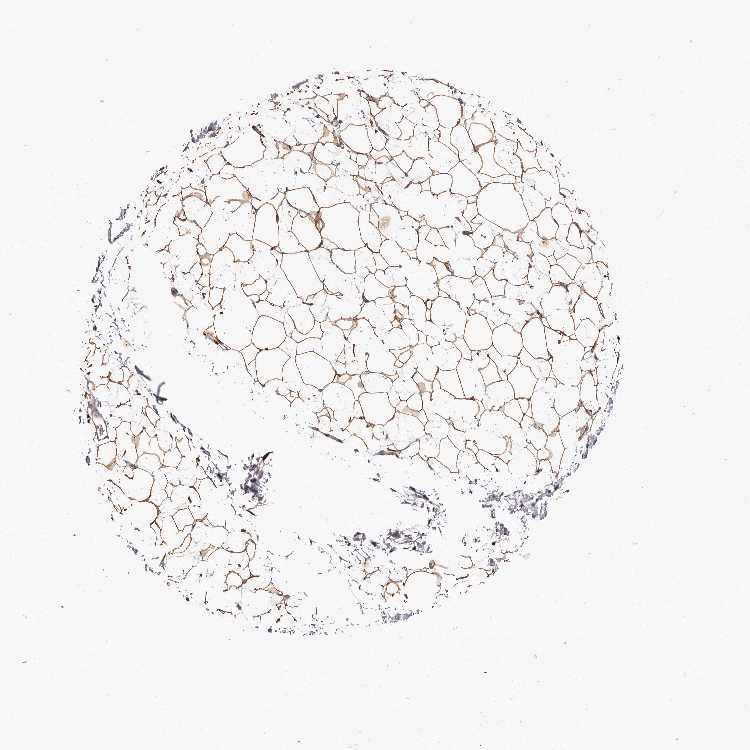

SOFT TISSUE 2 - Antibody stainingi

Antibody staining in the annotated cell types in the current human tissue is reported as not detected, low, medium, or high, based on conventional immunohistochemistry profiling in selected tissues. This score is based on the combination of the staining intensity and fraction of stained cells.

Each image is clickable and will lead to virtual microscopy that enables deeper exploration of all samples and also displays staining intensity scores, fraction scores and subcellular localization as well as patient and tissue information for each sample.

Antibody HPA027499Antibody HPA027511

Chondrocytes Not detectedMedium

Fibroblasts MediumNot detected

Peripheral nerve -Low